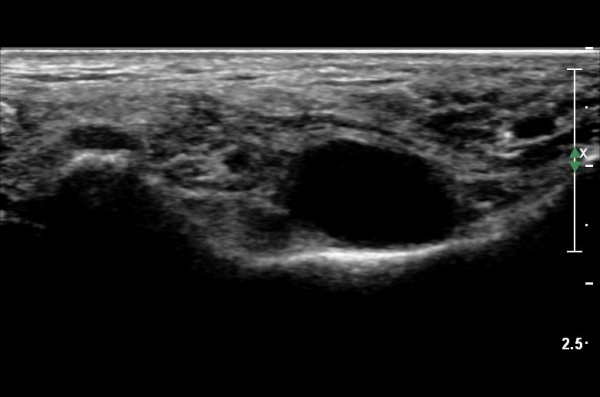

¹ß¸ñÅͳΠȾ´Ü¸é°Ë»ç¿¡¼­ ³»Ãø º¹»ç»À ³»Ãø¿¡ Èİæ°ñ°Ç, ¹ß°¡¶ô±¼°î°Ç°ú ¾öÁö¹ß°¡¶ô±¼°î°Ç

»çÀÌ¿¡¼­ Èİæ°ñ½Å°æÀÌ °üÂûµÇ°í ½Å°æÀÇ Ç¥Ãæ¿¡ µ¿¸Æ°ú Á¤¸ÆµéÀÌ °üÂûµÈ´Ù(»çÁø 1).